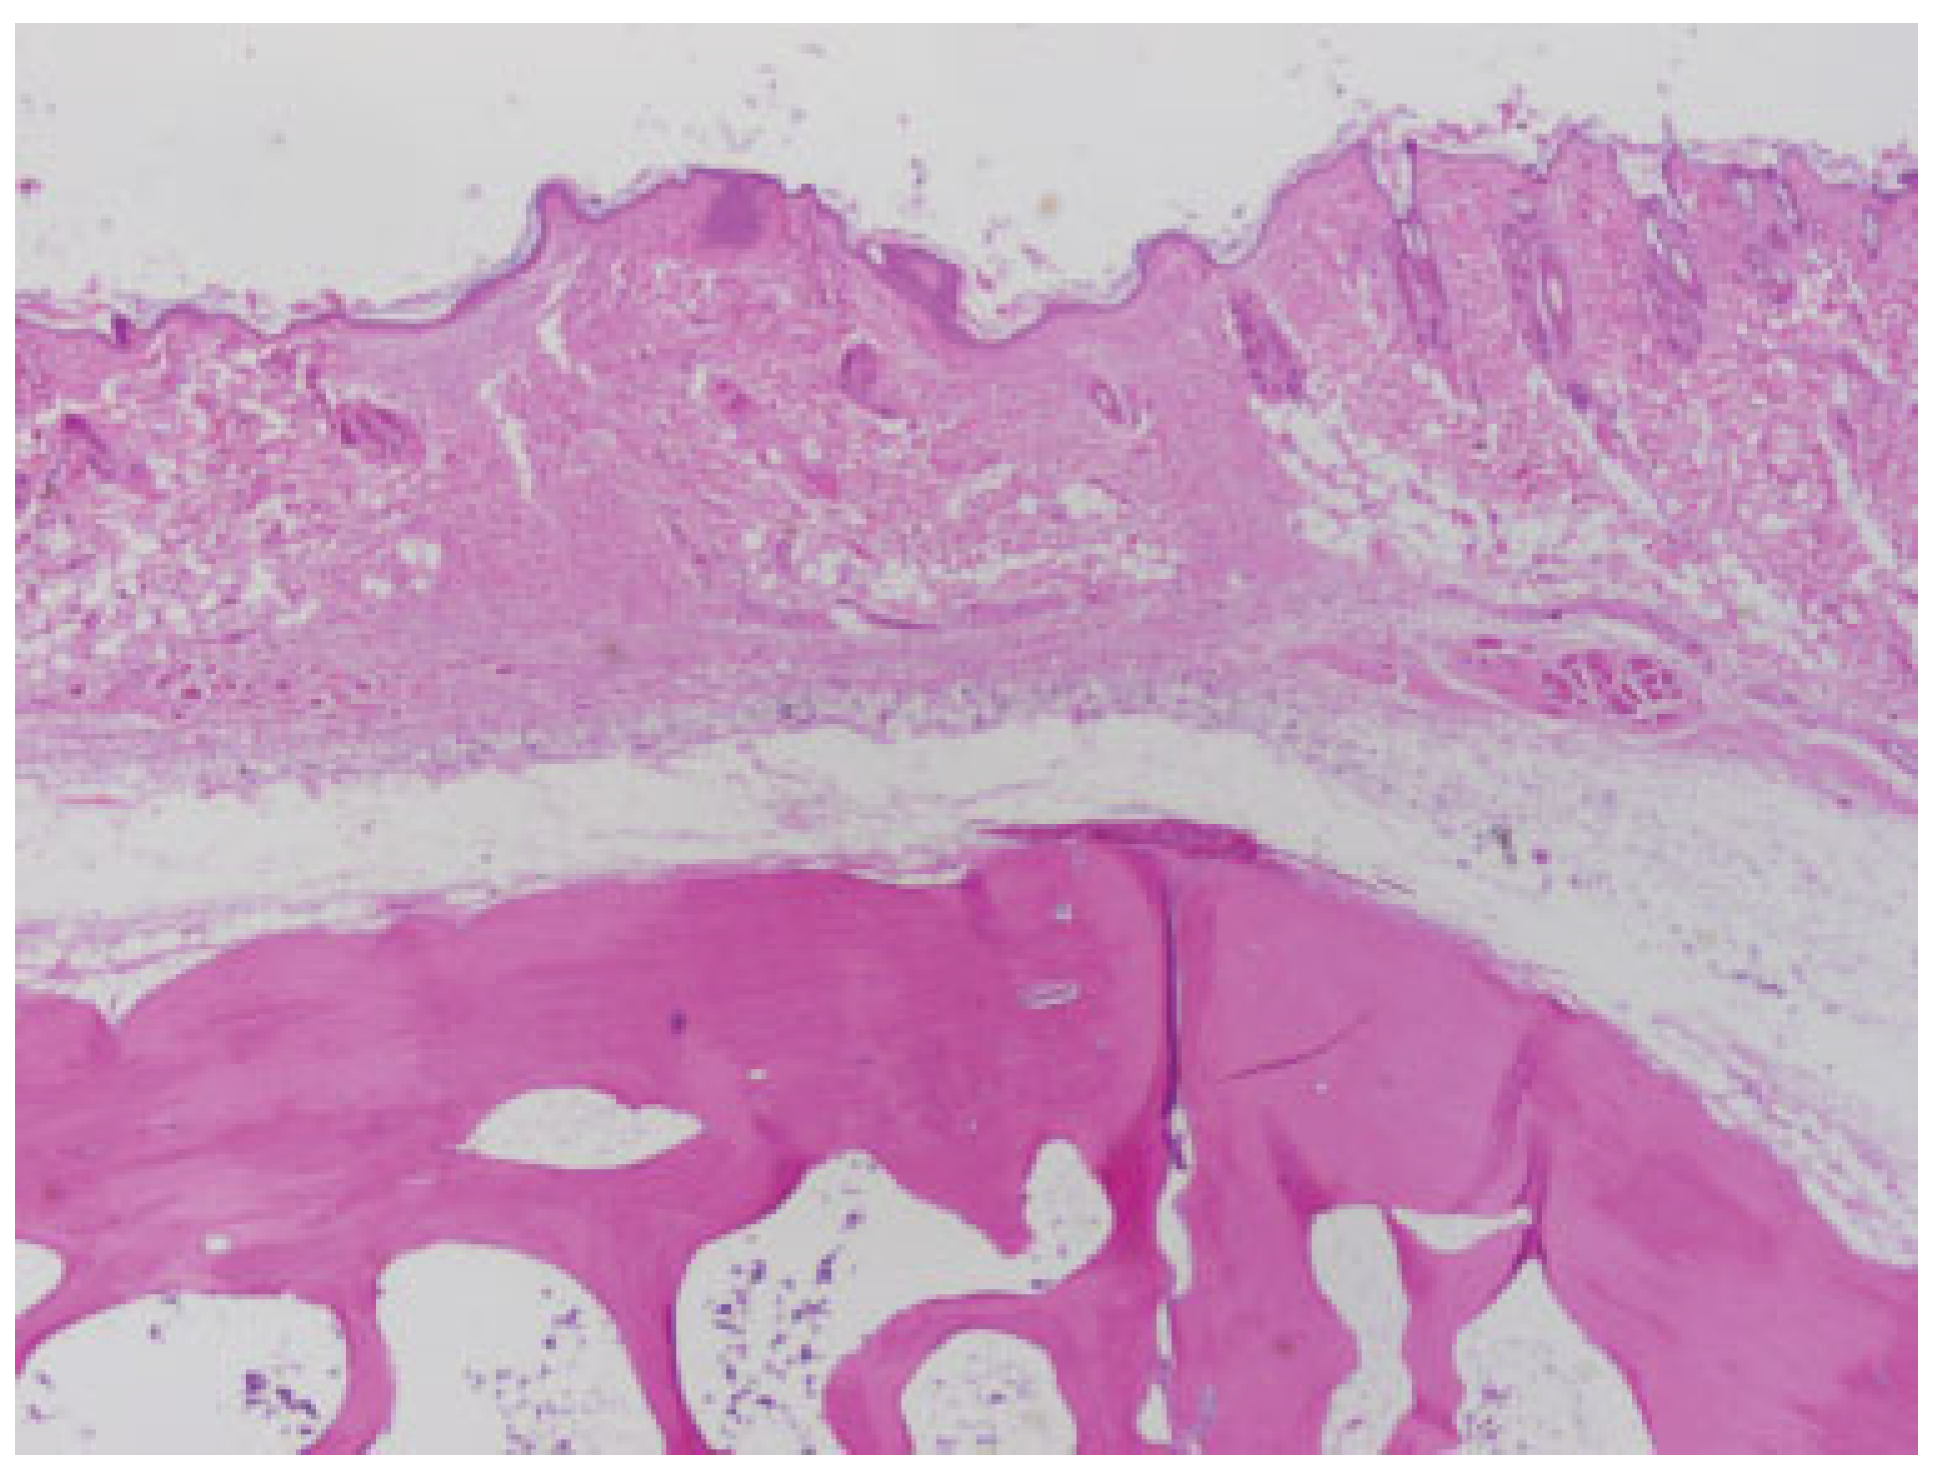

Poly-lactide-glycolic acid plate at 3 months postimplantation. The plate was epithelialized, but did not integrate into surrounding tissue. Note existence of a soft-tissue cavity which contained the implant. (light microscopy, hematoxylin and eosin stain, original magnification ×40).

Figure 8.

Poly-lactide-glycolic acid plate at 3 months postimplantation (light microscopy, hematoxylin and eosin stain, original magnification ×40, composite image approximating location of implant cavity). There was no evidence of implant fragments or local foreignbody reactions. Surrounding soft tissue and bone are histologically unremarkable. These findings persist in 6-month and 12-month samples.